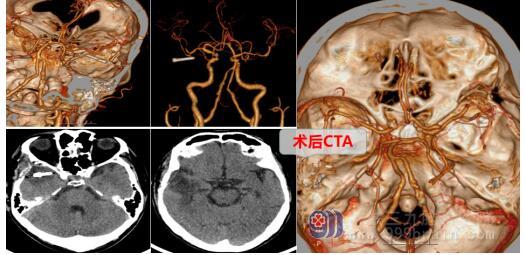

经主管医生向家属讲解手术风险和术后并发症,家属同意后,欧阳辉教授带领神经外十科医疗团队为蔡叔实施了“右侧大脑中动脉动脉瘤夹闭术”。术中,分离、显露大脑中动脉主干及其分支,在大脑中动脉分叉处见一囊状动脉瘤,予动脉瘤夹夹闭动脉瘤颈,荧光造影检查载瘤动脉及远端分支保护良好,血流通畅,动脉瘤不显影。术后,蔡叔安返病房,予康复、营养、对症治疗。